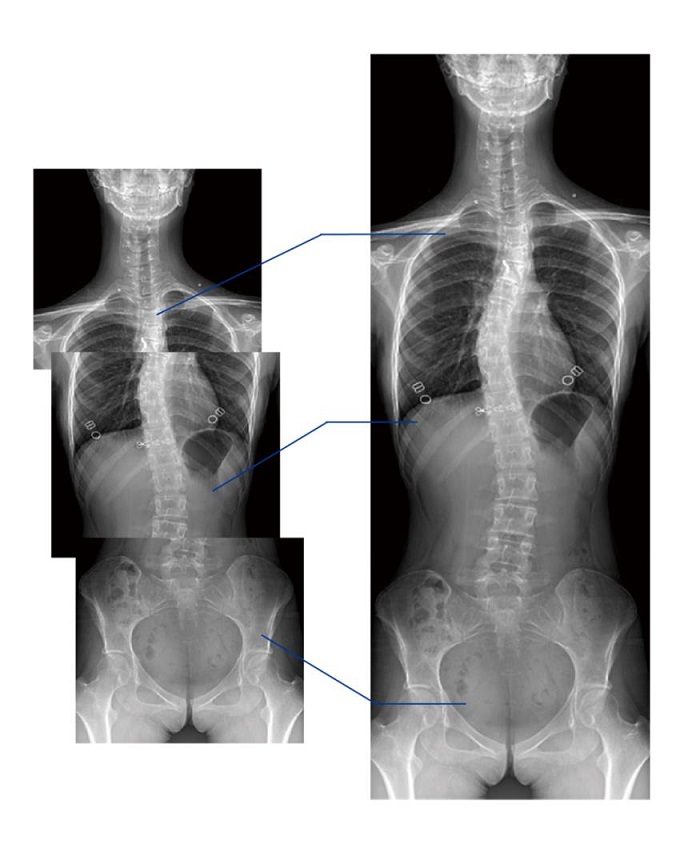

另外,動態(tài)DR的全景拼接功能,可通過對脊柱、下肢及下肢靜脈造影進(jìn)行分段攝片,然后對分段圖像進(jìn)行拼接,在一幅X光圖像上完整顯示全脊柱或下肢整體形態(tài)。對于骨科疾病患者的全脊柱、全下肢病變情況圖像展示更加具有完整性,有助于骨科疾病患者臨床診斷效果的提升。